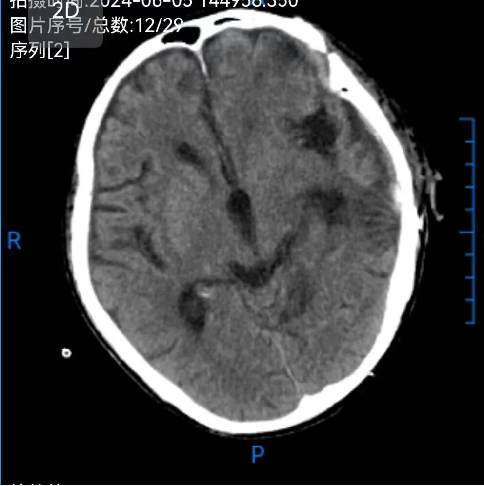

患者術後滿三個月(yuè)再次返院進(jìn)行顱骨缺損(sǔn)修補術,經過完善術前檢查、全(quán)科討論、做好充分手術(shù)準備後,武(wǔ)寧縣總醫院人民醫院院區神(shén)經外科團隊成功為患者完成(chéng)自體顱骨修補術(shù)。

術後: